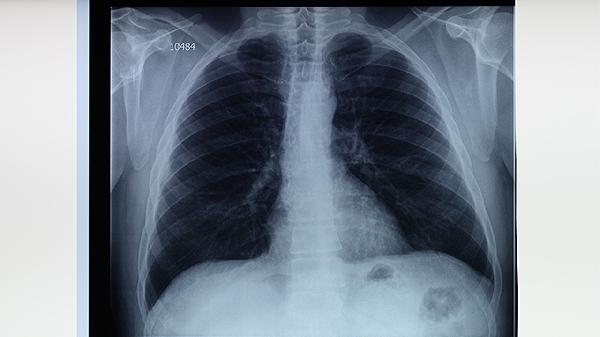

治疗期间每月需复查胸部X线或CT,监测病灶吸收情况。痰涂片检查每2周一次直至转阴,肝功能每月检测一次。出现咯血、持续发热等症状需立即复诊。治愈后仍需每半年随访1次,持续2年观察复发可能。